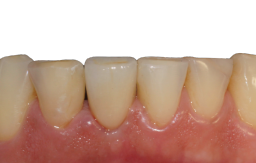

Na consulta seguinte, a coroa metalocerâmica foi instalada no elemento 41 e o orifício de acesso do parafuso foi restaurado com resina composta. Foi também realizada uma radiografia para posterior controle (Figuras 22, 23 e 24).

Após 12 meses, foi feita uma nova avaliação clínica e radiográfica, onde observou-se a boa manutenção dos tecidos peri-implantares (Figuras 25 e 26).